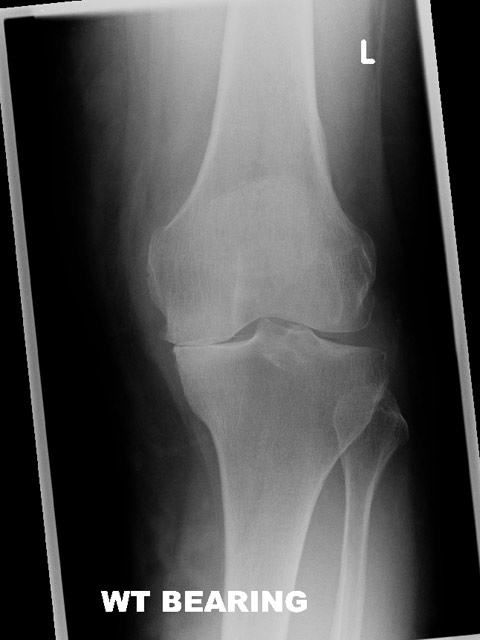

Before and After

Image Gallery

What is a knee replacement?

A knee replacement involves removing the worn joint surfaces from the top end of the shin bone and the bottom end of the thigh bone and sometimes the under surface of the knee cap. Metal and plastic components are cemented into the bone to fill the gap.